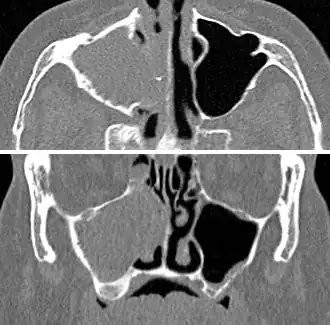

Imaging by either X-ray, CT, or MRI is generally not recommended unless complications develop.[66] Pain caused by sinusitis is sometimes confused for pain caused by pulpitis (toothache) of the maxillary teeth, and vice versa. Classically, the increased pain when tilting the head forwards separates sinusitis from pulpitis.[68]

For cases of maxillary sinusitis, limited field CBCT imaging, as compared to periapical radiographs, improves the ability to detect the teeth as the sources for sinusitis. A coronal CT picture may also be useful.[60]

Chronic

For sinusitis lasting more than 12 weeks, a CT scan is recommended.[66] On a CT scan, acute sinus secretions have a radiodensity of 10 to 25 Hounsfield units (HU). In a more chronic state, they become more viscous, with a radiodensity of 30 to 60 HU.[69]

-

CT of chronic sinusitis -

CT scan of chronic sinusitis, showing a filled right maxillary sinus with sclerotic thickened bone -

MRI image showing sinusitis. Edema and mucosal thickening appear in both maxillary sinuses. -

Maxillary sinusitis caused by a dental infection associated with periorbital cellulitis -

Frontal sinusitis -

X-ray of left-sided maxillary sinusitis marked by an arrow. There is a lack of air transparency, indicating fluid in contrast to the other side.